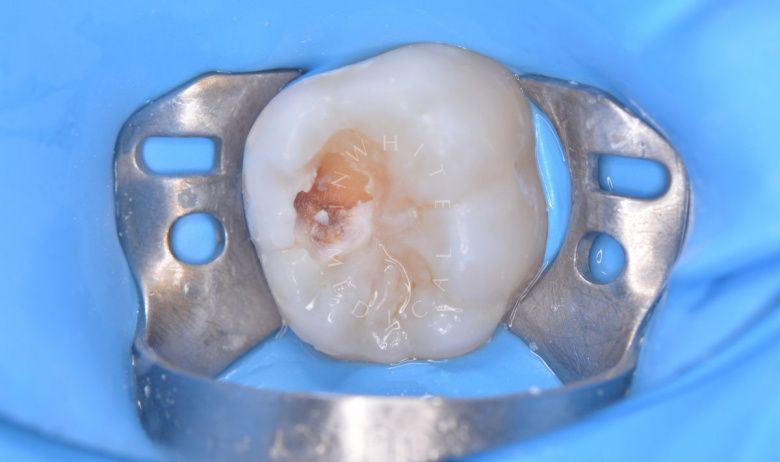

етская стоматология под наркозом Москва. Лечение молочных зубов и установка металлических коронок во сне - до процедуры